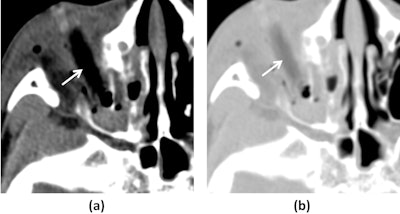

A 7-year-old boy, imaged 15 hours post-injury. Axial CT images with soft tissue windows (WW/WL=350/50) (a) reveal a rod-shaped foreign body (white arrow) situated along the course of the right inferior rectus muscle. The soft tissue window demonstrates that the foreign body exhibits attenuation similar to orbital emphysema. Axial CT images (WW/WL=1000/−200) at the same level (b) show that the attenuation of the foreign body (white arrow) is markedly different from that of the air in the sinuses. Image and caption courtesy of Dapeng Hao, MD, also of the Affiliated Hospital of Qingdao University.

"CT is the first choice for diagnosing [these objects, as its] window width of up to 1,000 HU optimizes visibility of intraorbital wooden fragments," the group noted.

- Hypoattenuation between the attenuation of fat and air was discovered in eight patients with intraorbital wooden foreign bodies, with a mean value of -252.77 HU (Hounsfield units) on CT.